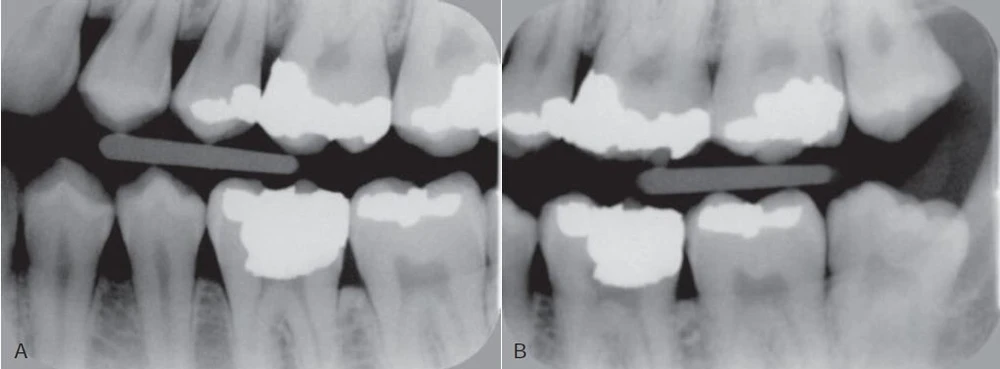

Phim X quang cận chóp (Hình 2) cho thấy khoảng dây chằng nha chu ở chóp chân gần răng 46 có hiện tượng dầy lên. Khám ngách hành lang tương ứng với chân răng cho kết quả âm tính, nhưng gõ dọc và gõ ngang đau ở răng 46. Thử tủy đáp ứng bình thường với nóng và lạnh ở tất cả các răng trừ 46. Răng này không phản với bất kỳ thử nghiệm tủy nào. Có thể kết luận răng 46 đã chết tủy và phải tiến hành điều trị nội nha. Nhưng nguyên nhân gì khiến chết tủy?

Hình 2: Phim cận chóp ban đầu.